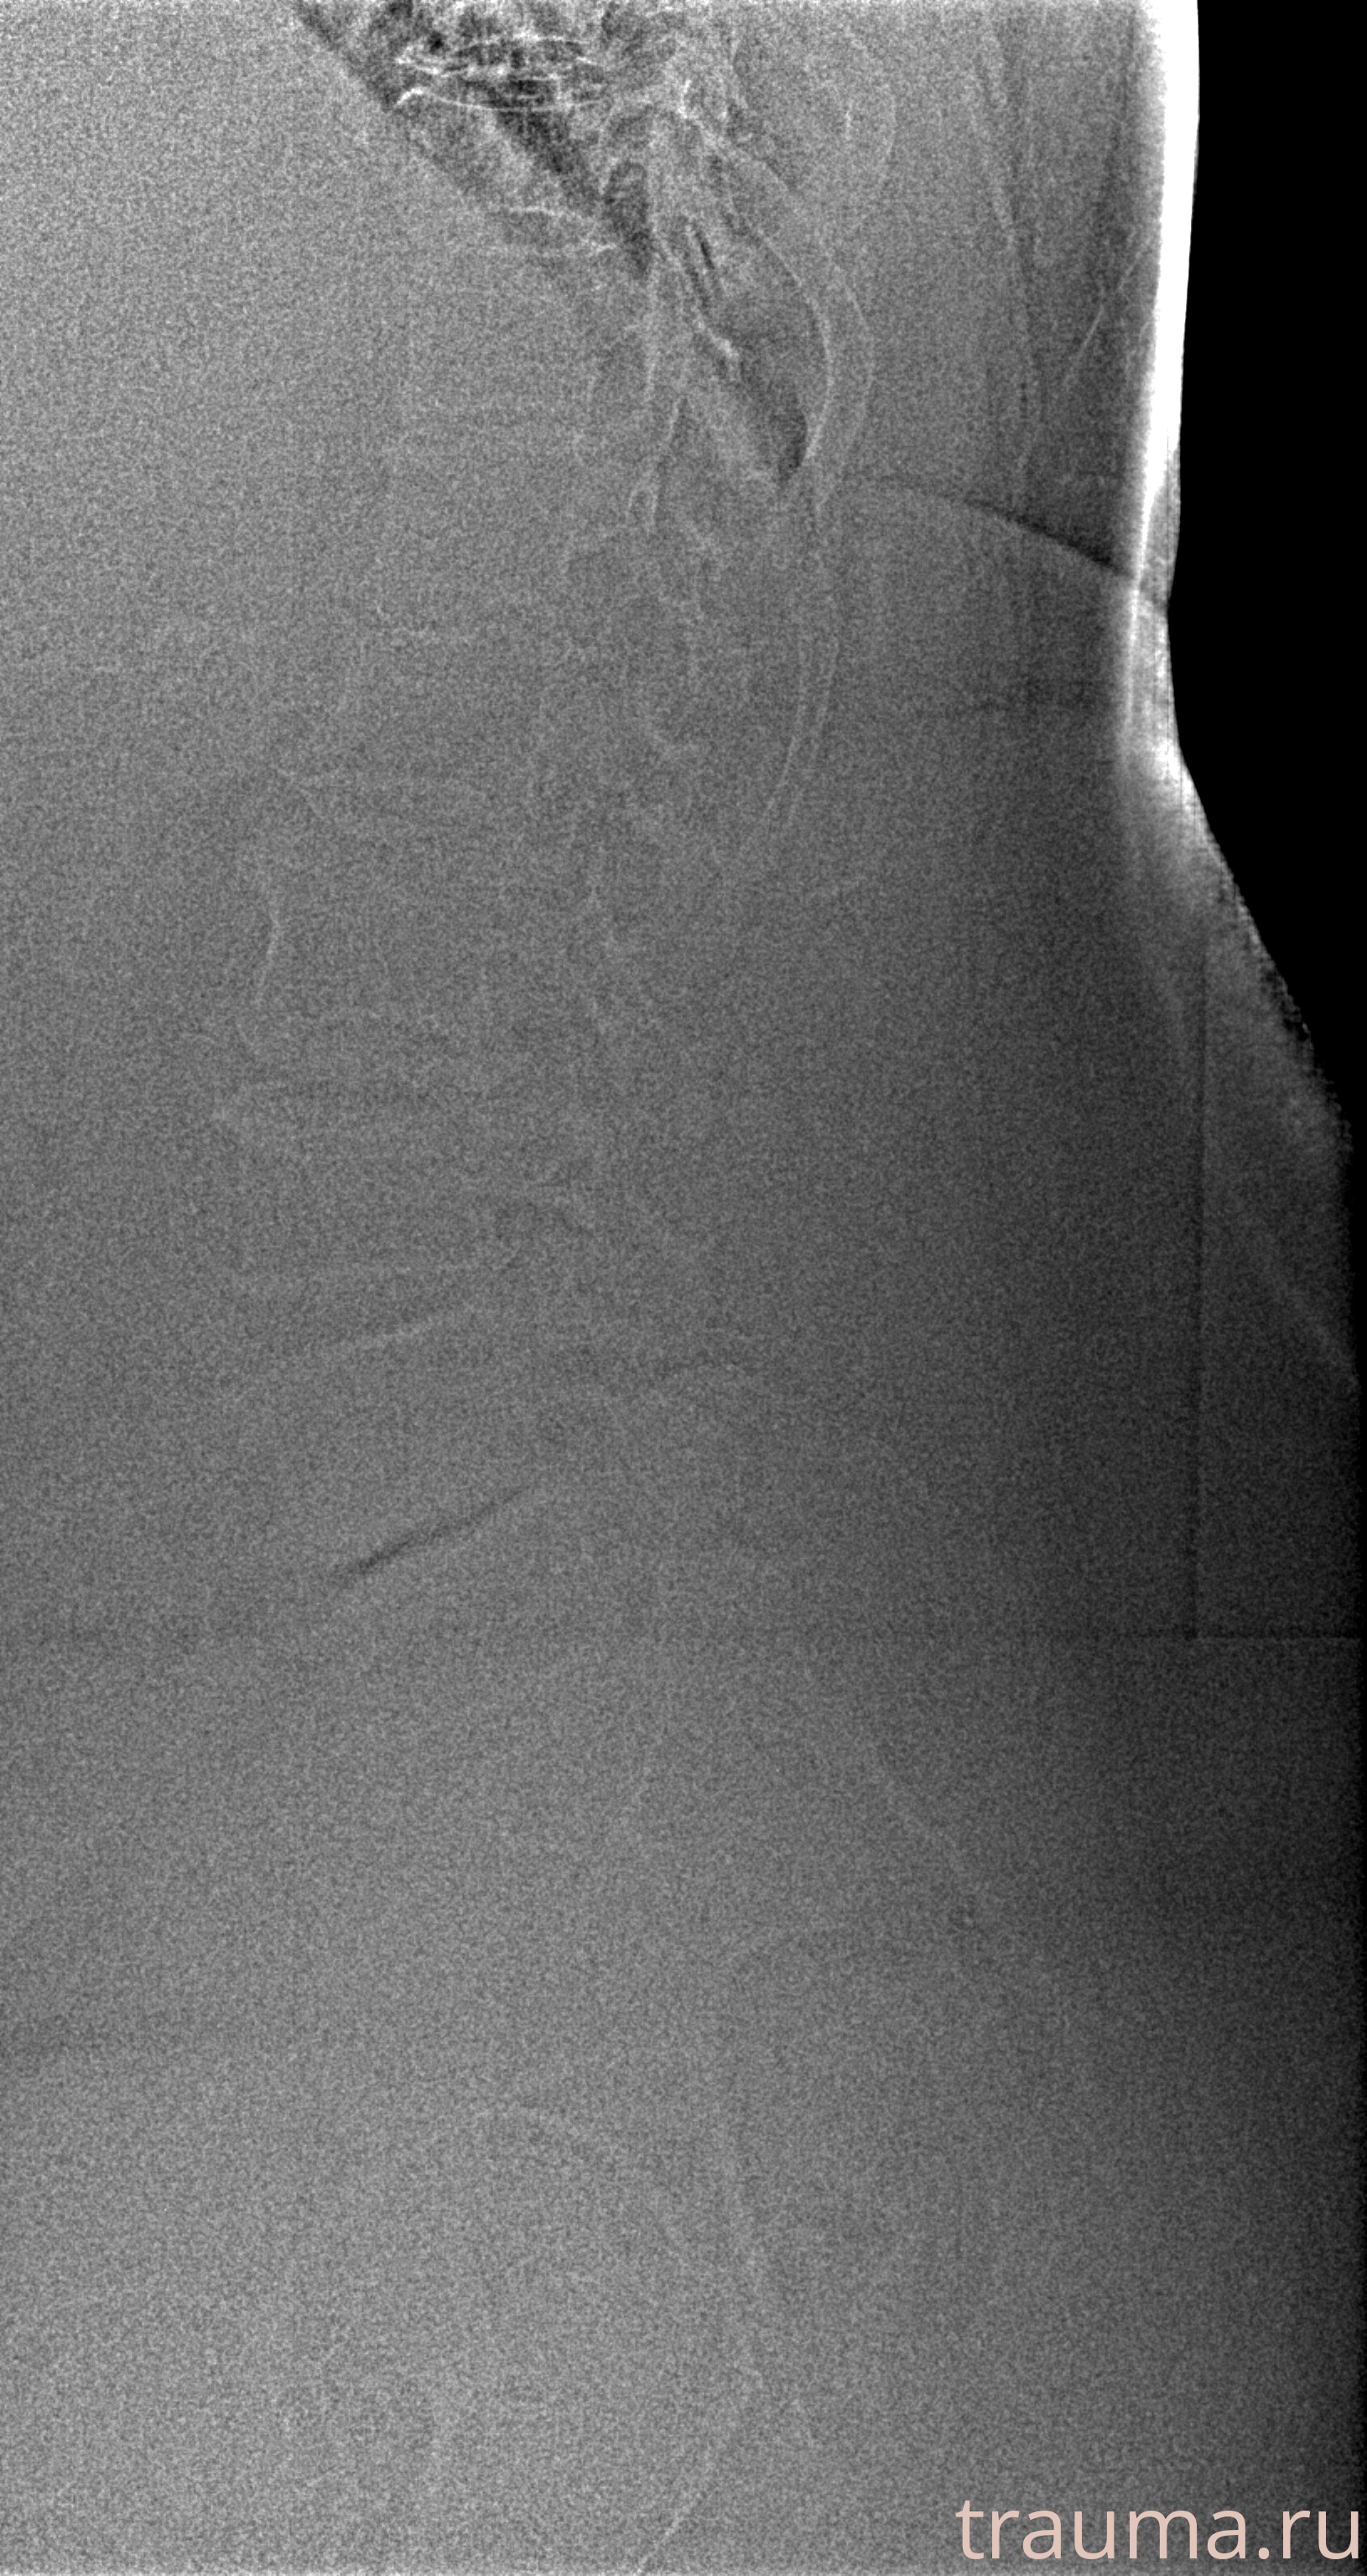

Рентгенограммы

Рентген на дому: по вашему адресу приезжает врач-рентгенолог, травматолог-ортопед с мобильным рентгеновским аппаратом, проводит диагностику травмы или заболевания, делает необходимые рентгенограммы, дает рекомендации по дальнейшему лечению. Получить качественные снимки в домашних условиях возможно благодаря уникальной методике, разработанной МосРентген Центром для института  Склифосовского